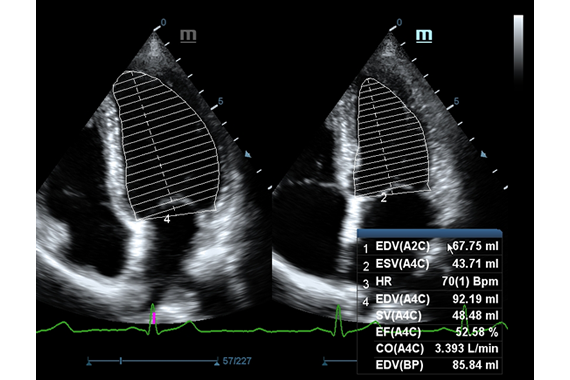

Thunder-speed imaging with X-Engine(CPU+GPU)X-Engine(CPU+GPU)에 의한 초고속 화상처리의 새로운 X-Engine은 GPU와 CPU 를 내장하고 있기 때문에 멀티코어의 병렬처리가 가능하고, 고속의 화상처리와 뛰어난 선명도를 실현합니다. 고도의이미징엔진으로 기존보다 3~4배 속도로 이미징 속도가 빨라지고 3D/4D 등의 애플리케이션을 통해 매우 빠르고 선명한 이미지를 보여줍니다. ![]() “Touch and Bingo” with premier transducers